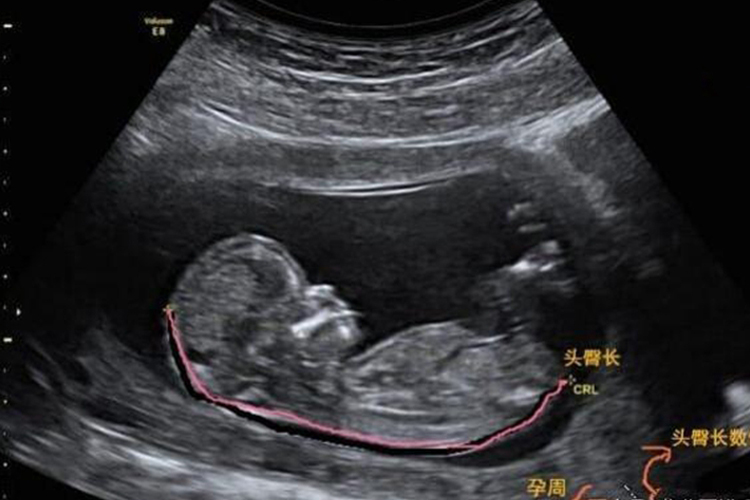

怀孕13周时,胎儿已经初具人形,并处于快速生长和发育的重要阶段。13周成型胎儿的具体特点,可以从外观特征、器官发育等方面进行描述。

- 身长:约65到79毫米(也有说法认为约10厘米或76毫米),具体数值可能因个体差异而有所不同。

- 体重:约13到30克(也有说法认为约25克),同样存在个体差异。

- 头部:头部约占身体的一半,面部形态已经完整,鼻子完全成形,并能支撑头部运动。

- 四肢:四肢已经发育得很好,手指和脚趾开始分开,并能进行简单的动作,如吮吸手指、玩脚趾等。